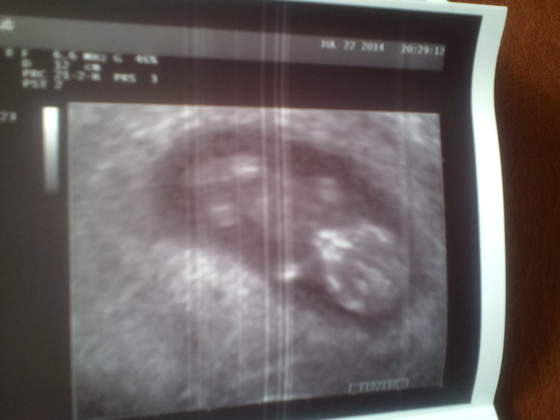

IMG_20151027_183425.jpgDziewczyny ja juz po wizycie. Kazal powtórzyć mocz i glukozę i dzwonić do niego z wynikami ale recepte na antybiotyk wypis al w razie czego ! Poza tym okej . USG zrobione, pięknie widać Malenstwo. Jest większe niż powinno bo odpowiada 10 tygodniowej ciazy choć nie wiem.dlaczego skoro dokladnie wiem kiedy bylo zaplodnienie?! Ale lepiej ze większe niz mniejsze prawda?? Ma 2.2 cm piękne raczki i nóżki oraz pępowine! Jestem taka szczęśliwa ze wszystko jest dobrze..... kochane do roboty bo piękny czas przed Wami!!

• IMG_20151027_183425.jpg

IMG_20151027_183425.jpg

23,2 KB · Wyświetleń: 112